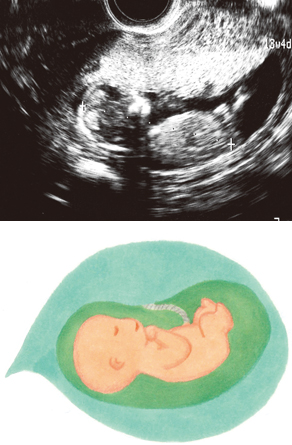

妊娠13週ころのエコー写真を見てみよう

胎盤に厚みが出てきます

赤ちゃんの上側に見える、白く厚みのあるものが胎盤です。胎盤の完成まであと少しになりました。写真は、胎盤の中央あたりから、へその緒が出ていることも確認できます。